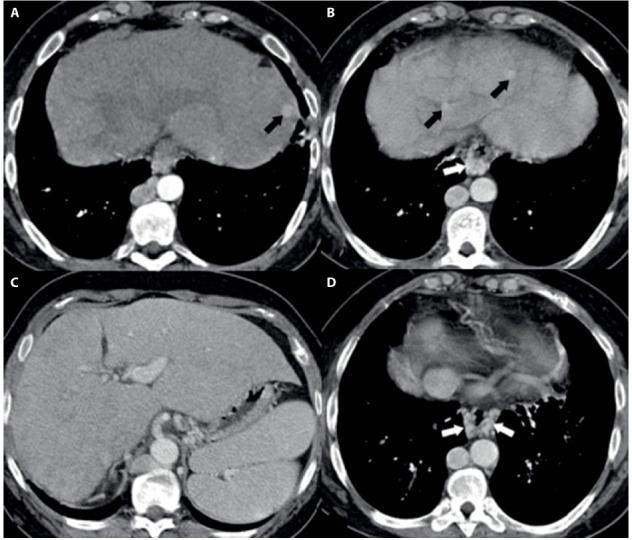

多模态影像学评估罕见且复杂的单心室生理学病例;心脏磁共振的重要作用。

Multi-modality Imaging Evaluation of a Rare and Complex Case of Single Ventricle Physiology; the important role of Cardiac MR.

Congenital heart diseases (CHD) represent a major clinical and diagnostic challenge for correct abnormality identification and subsequent successful therapy; even more challenging is following-up patient health after multiple post-interventional corrections often required in complex cardio-vascular abnormalities. We describe a multi-modality imaging evaluation of a complex congenital cardio-vascular diseases, underlining the relevance of cardiac magnetic resonance to non invasively solve some issues related to postsurgical changes.

先天性心脏病(CHD)是正确识别异常并随后成功治疗的主要临床和诊断挑战;更具挑战性的是在复杂心血管异常通常需要多次介入矫正后,对患者健康进行随访。我们描述了一种复杂先天性心血管疾病的多模态成像评估,强调心脏磁共振在无创解决与手术后变化相关的一些问题方面的相关性。